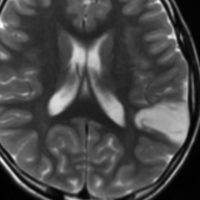

10代の少女に見つかったDNTです。難治性のてんかんがあり1日になんども意識減損を生じて,けいれんを止める薬をたくさん飲んでいて副作用のために眠気で日常生活が困難でした。でも,他の症状は何もありませんでした。左の頭頂葉と側頭葉と後頭葉の境目にできたものです。おそらくお母さんのお腹の中いたときからあった腫瘍なので何もしないで様子を見てもいいのです。でも,てんかん発作がひどいので腫瘍だけを摘出しました。DNTだけを取っても後遺症が残ることはほとんどありません。この場所は周囲の脳組織をとると後遺症がでる場所 (eroquent area)なので,てんかんを止める目的でもかなりの理由がないと周囲の脳組織は摘出しません。この子は,抗てんかん薬もいらなくなって完治しました。